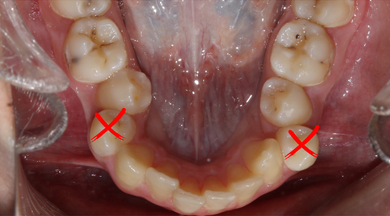

کشیدن دندان در ارتودنسی برای بسیاری از متقاضیان درمان ارتودنسی، مبهم است. شاید از نظر بیماران انجام این کار غیر معقول به نظر برسد اما زمانی که فرد با تراکم و ازدحام دندان در دهان مواجه باشد و در داخل دهان فضای کافی برای هدایت دندانها به جای اصلی وجود نداشته باشد، لازم است یک الی چند دندان کشیده شود. پزشک معالج با بررسی کامل دندانها و به کمک تصاویر رادیولوژی تصمیم میگیرد که آیا ضرورتی در کشیدن دندان برای ارتودنسی وجود دارد یا خیر. چنانچه در قوس دندانی فضای کافی وجود نداشته باشد و یا اگر دندان نهفته ای داشته باشید، کشیدن دندان به احتمال زیاد انجام میشود. به هم فشردگی دندانها گاهی آنقدر شدید است که تمام دندانها در قوس جا نمیشوند و بنابراین کشیدن دندان لازم میباشد. اما باید توجه داشت که فضای خالی ناشی از کشیدن دندانها طی درمان ارتودنسی کاملاً بسته میشود.